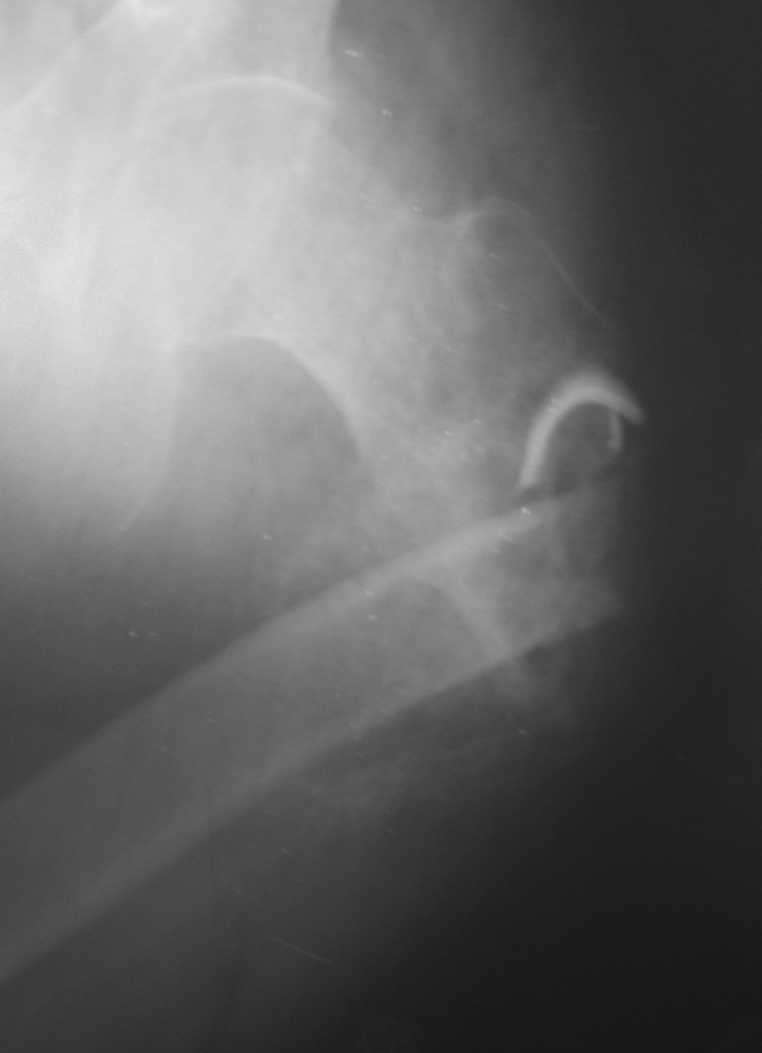

[Ortho] Неправильно консолидирующийся перелом бедра

Пациент 34 лет бомж получил травму окло 1,5-2 мес назад. За мед помощью не обращался. При

поступлении левая нижняя конечность резко ротирована кнутри, варусная деформация бедра.

По наружной поверхности рана 2 на 2 см с незначительным серозно гнойным

отделяемым,умеренными грануляциями, в ране дистальный отломок бедреной кости.

Патологическая подвижность в области перелома назначительная. Проведена попытка репозии

дистракционным аппаратом, с незначительным эффектом (несколько уменьшилась внутренняя

ротация.Что делать дальше? Остеотомия? Санация гнойного очага